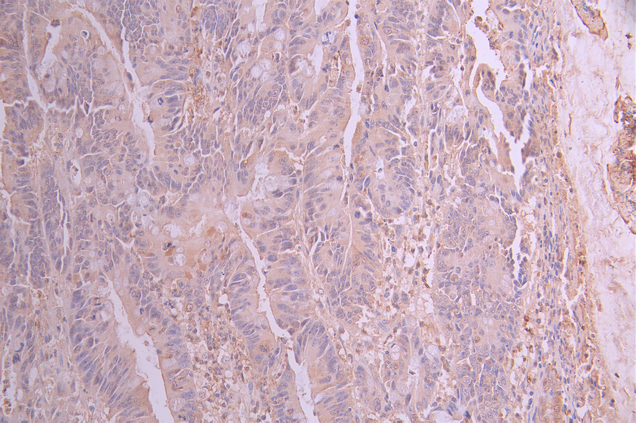

IHC image of CSB-RA136847A0HU diluted at 1:100 and staining in paraffin-embedded human colorectal cancer performed on a Leica BondTM system. After dewaxing and hydration, antigen retrieval was mediated by high pressure in a citrate buffer (pH 6.0). Section was blocked with 10% normal goat serum 30min at RT. Then primary antibody (1% BSA) was incubated at 4°C overnight. The primary is detected by a Goat anti-rabbit polymer IgG labeled by HRP and visualized using 0.05% DAB.